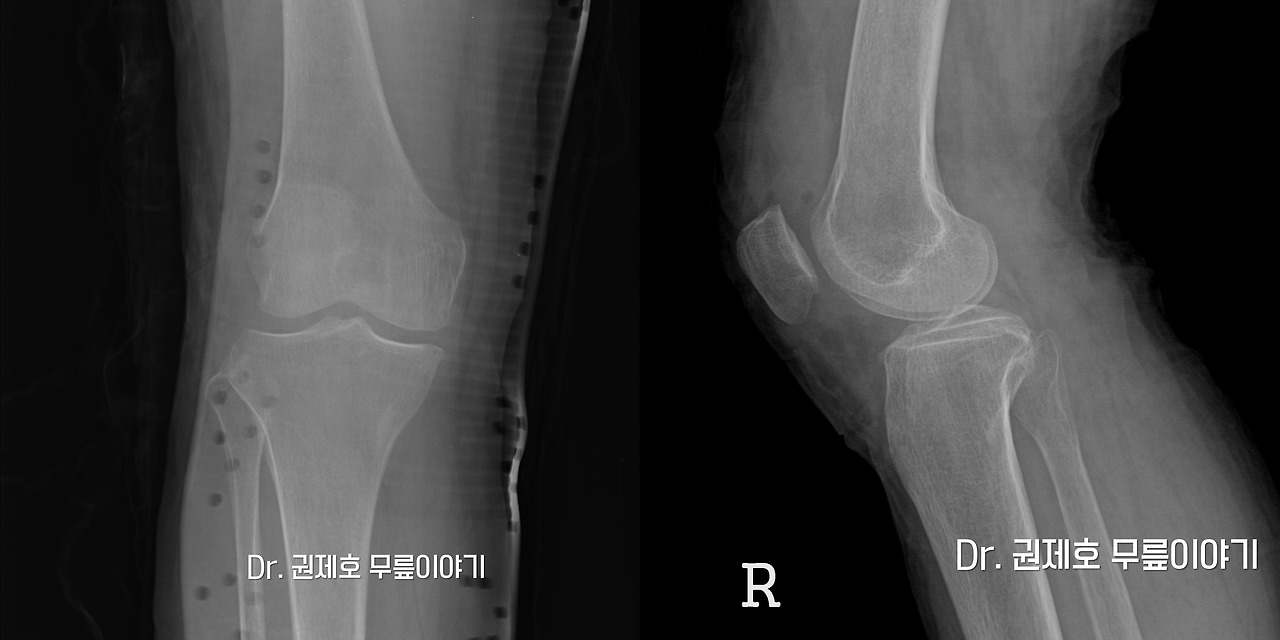

무릎연골줄기세포치료 (13).jpg

이 분의 경우 사진을 보면 사진에 뼈가 자라난 소견이 관찰되고 있습니다. 이는 무릎이 더 이상 힘을 받지 못해서 자라는 뼈로 골극이라고 표현을 합니다. 뒤에서 바라본 사진으로 로젠버그 사진이라고 표현을 하는데 이는 실제 걸을 때 무릎에 가해지는 현상을 반영하는 사진으로 무릎 연골에 결손이 있어 관절염이 진행된 분들에게 유용한 사진입니다. 이 분의 경우를 보면 관절 간격에 감소는 미미하게 관찰되고 있습니다.